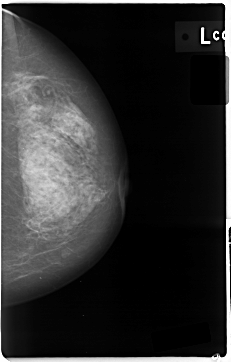

C_0004_1.LEFT_CC

LEFT_CC LINES 4704 PIXELS_PER_LINE 3000 BITS_PER_PIXEL 12 RESOLUTION 50 NON_OVERLAY